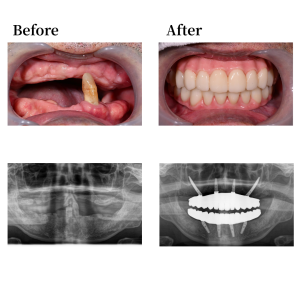

上顎骨の形状を整え、12,22の位置にノーマルインプラントを0度垂直埋入。15, 25 の位置にザイゴマインプラントを45度傾斜埋入。下顎も形状を整え、45, 42, 32, 35の位置にそれぞれオールオン4インプラントを埋入。 42, 32の位置に、0度垂直埋入、45, 35の位置に17度傾斜埋入。その後、マルチユニットアバットメントで角度補正を行い、プロビジョナルレストレーション(審美的な仮歯)を装着した。

上下顎はUTジルコニアで構成された、フルジルコニアブリッジでファイナルレストレーションとした。焼成されたジルコニアはステインテクニックで着色した。シェードカラーはA1。